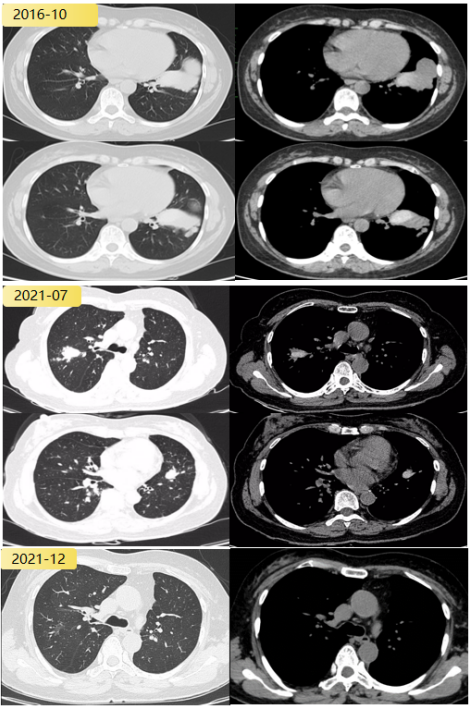

患者,女性,33岁,主因「反复咳嗽、胸闷7年,发现肺部病变3月」于2022年4月第二次入院。既往激发试验阳性,诊断为支气管哮喘,自诉「咳果冻样痰」,查白细胞计数8.74×10^9/L,嗜酸性粒细胞比值5.9%(↑),绝对值0.5×10^9/L。lgE 593.95 IU/ml。外送烟曲霉特异性IgE阴性,烟曲霉IgG阴性。

气管镜:左内前基底段条状分泌物。影像学可见指套状物。

abp在医学是什么意思2021日本ABPA/ABPM诊断标准解读_https://www.jmylbn.com_新闻资讯_第14张

abp在医学是什么意思2021日本ABPA/ABPM诊断标准解读_https://www.jmylbn.com_新闻资讯_第15张

患者无鼻窦炎、无支气管扩张、无曲霉致敏证据。但符合日本ABPM诊断标准。患者按照ABPM治疗,复查胸部CT有吸收,目前仍在随访中。